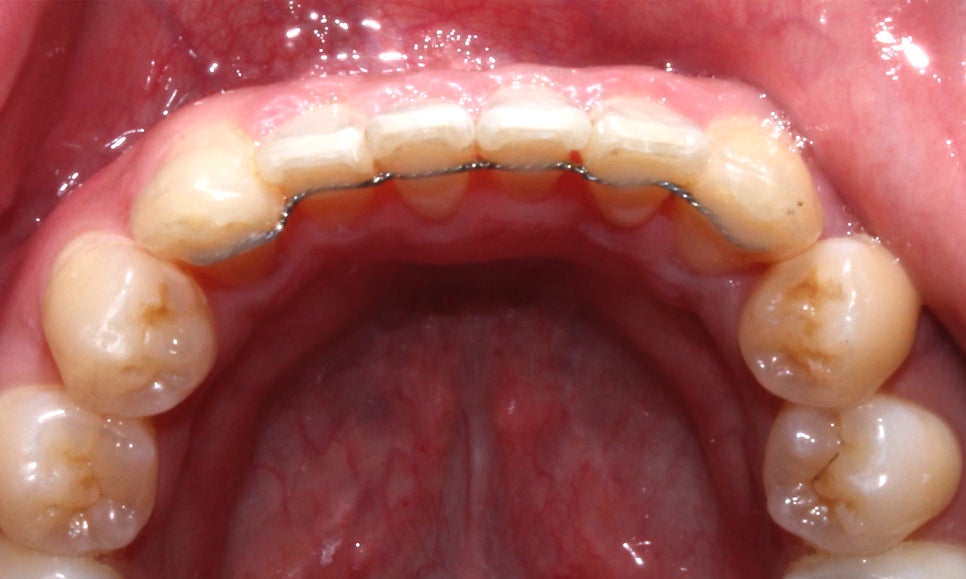

부분 교정에 사용되고 있으며 환자분께서는

상하악 전치부만 2D교정을 진행하셨습니다!

이 점 유의하여 포스팅을 읽어주세요^^

2D교정은 일반적인 설측교정 장치보다

훨씬 작고 얇기 때문에 교정장치의 착용감,

혹은 발음 상의 문제를 걱정하시는 경우

추천드리는 교정 장치입니다~